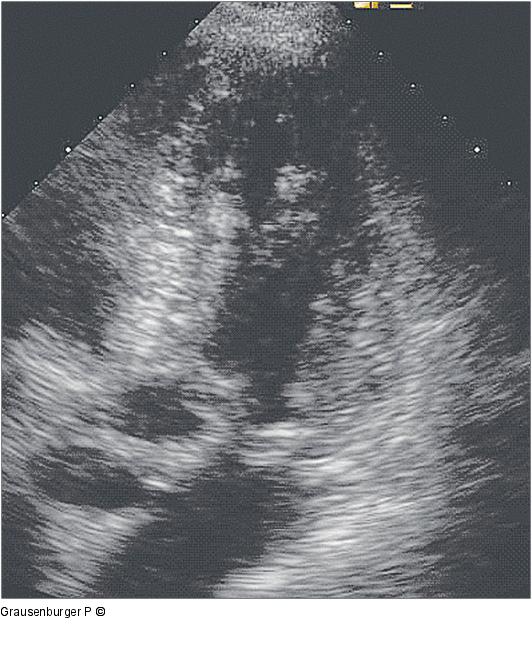

Abbildung 1: Hypertrophe CMP Hypertrophe CMP im apikalen Vierkammerblick, SAM-Phänomen |

Hypertrophe CMP im apikalen Vierkammerblick, SAM-Phänomen |